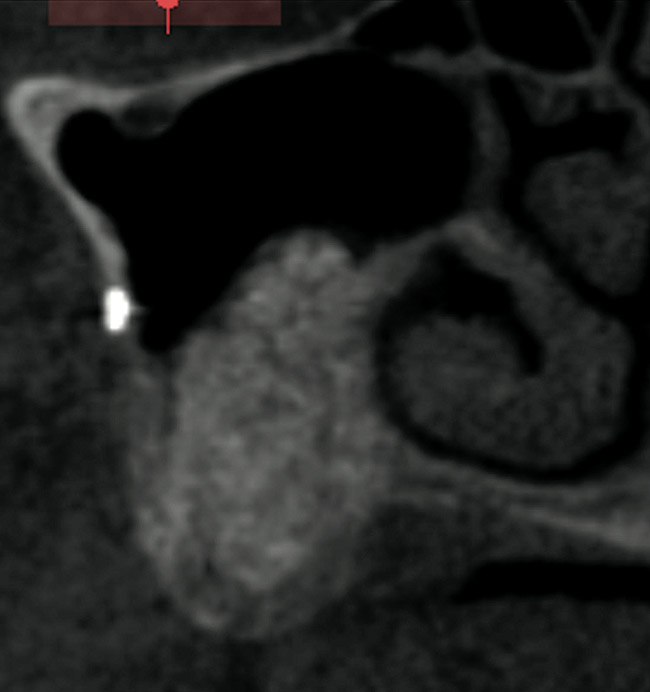

Figure 3  CBCT sagittal view. Note the extent of alveolar ridge deficiency.

Figure 3

Figure 8  Post-augmentation CBCT sagittal view (7 months).

Figure 8

Figure 10  Two-year post completion, CBCT sagittal view.

Figure 10